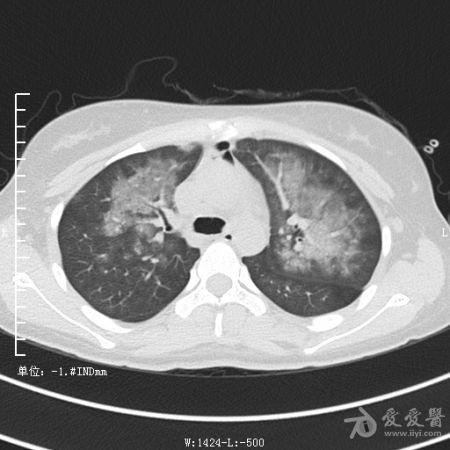

典型支气管扩张及肺水肿CT片

典型支气管扩张肺水肿